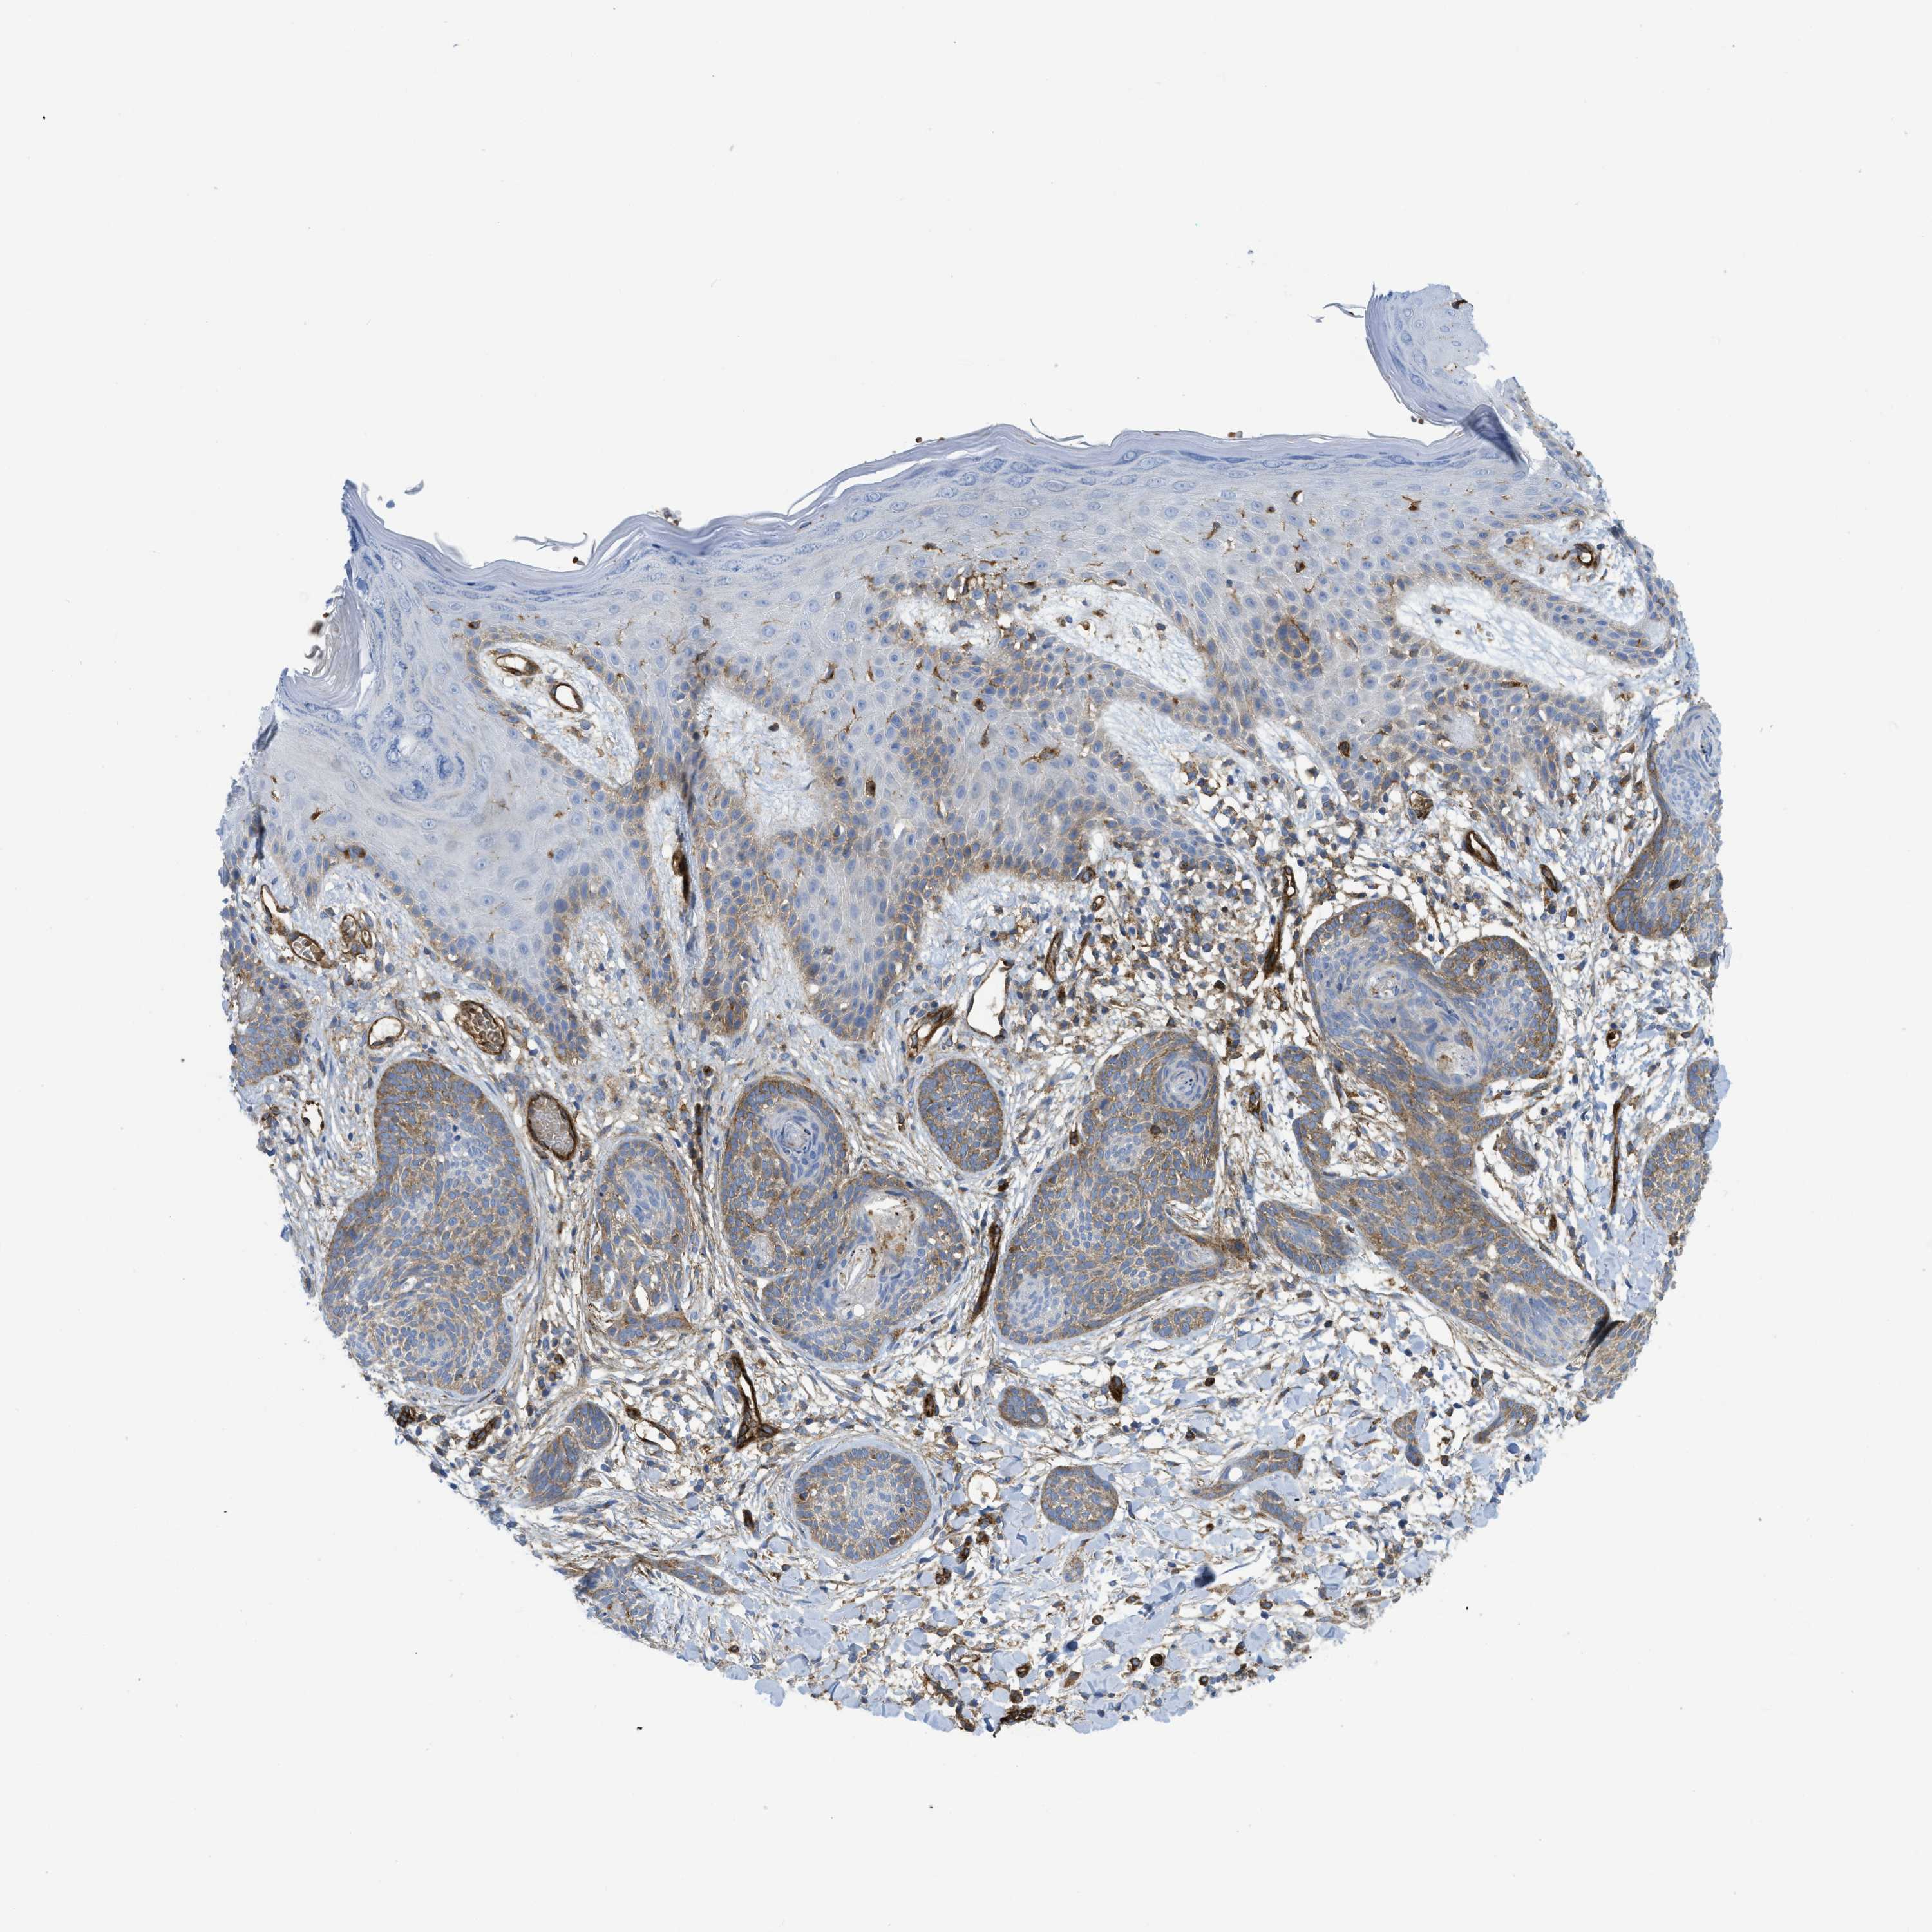

SKIN CANCER - Protein expressioni

A mouse-over function shows sample information and annotation data. Click on an image to view it in a full screen mode. Samples can be filtered based on level of antibody staining by selecting one or several of the following categories: high, medium, low and not detected. The assay and annotation is described here.

Each image is clickable and will lead to virtual microscopy that enables deeper exploration of all samples and also displays staining intensity scores, fraction scores and subcellular localization as well as patient and tissue information for each sample.

Antibody CAB015334

Staining

High

Medium

Low

Not detected

Intensity

Strong

Moderate

Weak

Negative

Quantity

>75%

75%-25%

<25%

None

Location

Nuclear

Cytoplasmic/membranous

Cytoplasmic/membranous,nuclear

Squamous cell carcinoma in situ, NOS

Squamous cell carcinoma, NOS

Squamous cell carcinoma, metastatic, NOS

Basal cell carcinoma

Adnexal tumor, benign